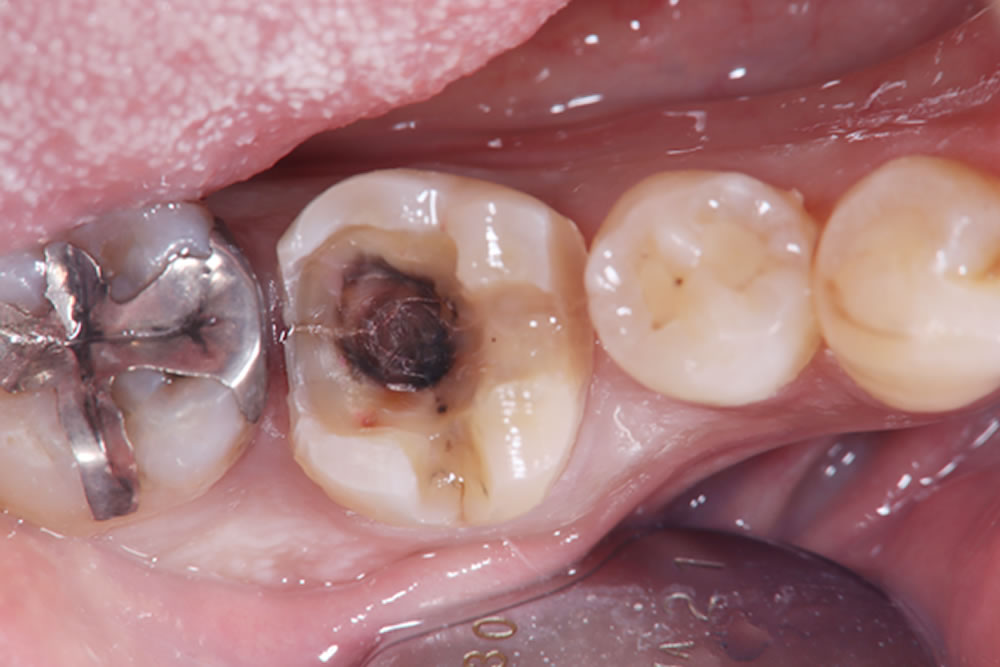

当該歯のメタルインレーを除去したところ、歯の内部に2次カリエス(虫歯の再発)を認めました。

う蝕検知液(虫歯部分に着色する薬液)を使用しながら、慎重に虫歯除去を行ったところ、遠心に歯根破折を確認しました。歯周ポケットが深かった部位と破折線が一致しており、このままつめ物を装着しても予後不良となる可能性があることを患者さまに説明したところ、抜歯とインプラントによる治療を希望されました。